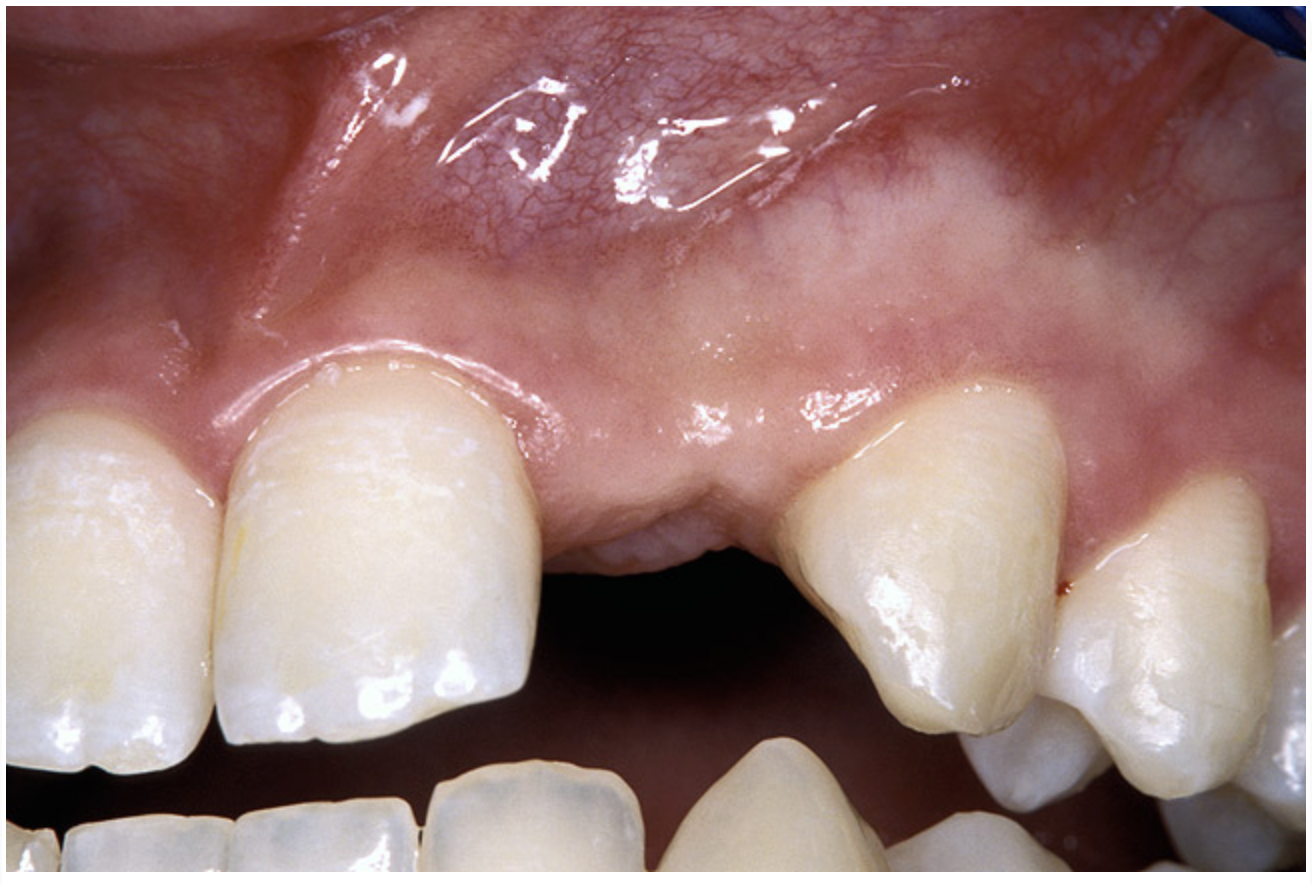

Periapical radiographs were taken to help determine the mesial-distal inclinations of the adjacent tooth roots (Figure 1). The radiographs revealed a serious issue, convergent roots for the right canine and right central, which eliminated that area as a potential implant-receptor site. The space between the left central and canine teeth was minimal, although the roots were relatively parallel. Clinical examination (manual palpation of the root eminences superiorly to the vestibule on the right side) confirmed the root convergence (Figure 2A). The flat, wide zone of the keratinized tissue and lack of interdental papilla was evident for the missing right lateral incisor. There was a marked difference in clinical appearance for the left lateral, which could impact the eventual plan of treatment (Figure 2B). Other significant clinical findings included bilateral facial bone concavities, which existed as a result of the congenitally missing tooth roots. As a diagnostic cue to the underlying bone topography, it is important to follow the demarcation between attached and unattached gingival tissue, and note the crestal width of the available keratinized tissue (Figure 2C).

Figure 2a  Pretreatment buccal views showed (A) root convergence, (B) a difference in clinical appearance of the left lateral, and (C) significant crestal width of keratinized tissue.

Figure 2a

Figure 2b  Pretreatment buccal views showed (A) root convergence, (B) a difference in clinical appearance of the left lateral, and (C) significant crestal width of keratinized tissue.

Figure 2b

Figure 2c  Pretreatment buccal views showed (A) root convergence, (B) a difference in clinical appearance of the left lateral, and (C) significant crestal width of keratinized tissue.

Figure 2c